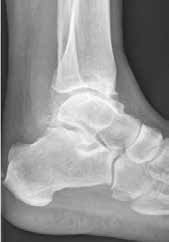

Endoprothetik des OSG

Die Indikation zur endoprothetischen Versorgung einer OSG-Arthrose ist gründlich zu stellen. Darunter fällt die schwere Arthrose jeglicher Ätiologie mit täglich intensiven Schmerzen, hochgradigem Gelenkfunktionsverlust und Gelenkdestruktion. Voraussetzungen sind eine gute Knochenqualität sowie mittleres Alter ohne schwere systemische Vorerkrankungen. Auch bei der Implantation von Endoprothesen des oberen Sprunggelenkes ist es wichtig, bestehende Achsfehlstellungen entweder in gleicher Sitzung oder zuvor zu korrigieren. Sofern nach Achskorrektur die Versorgung mittels einer Endoprothese noch notwendig ist, soll damit die Funktionsfähigkeit des Gelenks, eine Schmerzeliminierung und eine Verbesserung der Lebensqualität erreicht werden (Abb. 6). Kontraindikationen sind neben den bereits oben genannten: bestehende Osteonekrosen, periphere arterielle Verschlusskrankheit, periphere Neuropathie, bestehende oder stattgehabte Gelenkinfektion und schwere Bandinstabilität 56.

Im Vergleich zur Endoprothetik des Hüft- und Kniegelenks bestehen höhere Komplikationsraten bei der Endoprothese des Sprunggelenks. Intraoperativ sind dies meist operationstechnische Komplikationen bei der Osteotomie der Malleoli, beim Sägen oder beim Positionieren der Prothesenkomponenten 57. Postoperativ sind dies vornehmlich Wunddehiszenzen und Infektionen 58, während im Langzeitergebnis aseptische Prothesenlockerung, periprothetische Stressfrakturen und Retraktion der Gelenkkapsel sowie der periartikulären Weichteile auftreten 59.